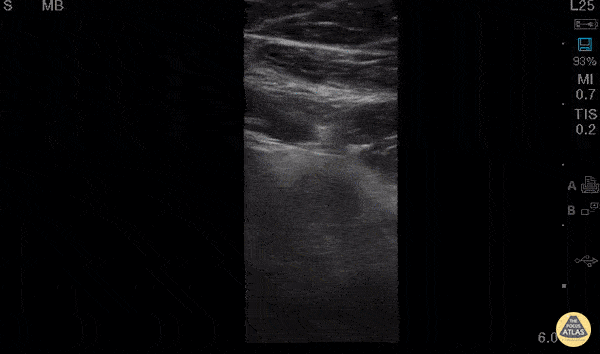

30 y/o M w/ subjective fever, RLQ pain x1day. Tenderness in McBurney’s point w/positive Rovsing’s and Psoas signs, labs significant for mild leukocytosis. POCUS w/ linear probe placed on area of maximal tenderness in RLQ. Transverse and longitudinal views demonstrated non-compressible, blind-ended, non-peristalsing, tubular structure with surrounding hypoechoic free fluid. A central hyperechoic structure representing a fecalith can be appreciated. Outer diameter was measured to be 10mm representing dilated appendix. Findings of acute appendicitis were confirmed with official ultrasound and pt was taken to OR for appendectomy without CT (limiting radiation for young adult). While POCUS is operator dependent and CT is gold-standard for diagnosis of appendicitis in adults, our POCUS findings had higher positive-predictive value given high pre-test probability (classic sx of appendicitis, alternate diagnoses less likely) and optimal pt for study (thin male, no prior surgeries). Dr. Robert Allen and Dr. Matthew Riscinti - Kings County Emergency Medicine